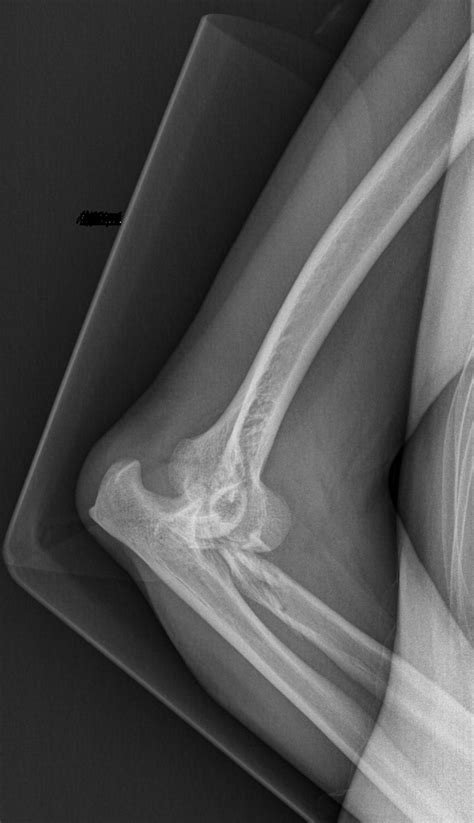

• Imaging Tests: X-rays or other imaging tests may be ordered to assess the extent of the injury and check for any associated fractures.

• Imaging Tests: Ordering X-rays or other imaging tests to check for any underlying issues.